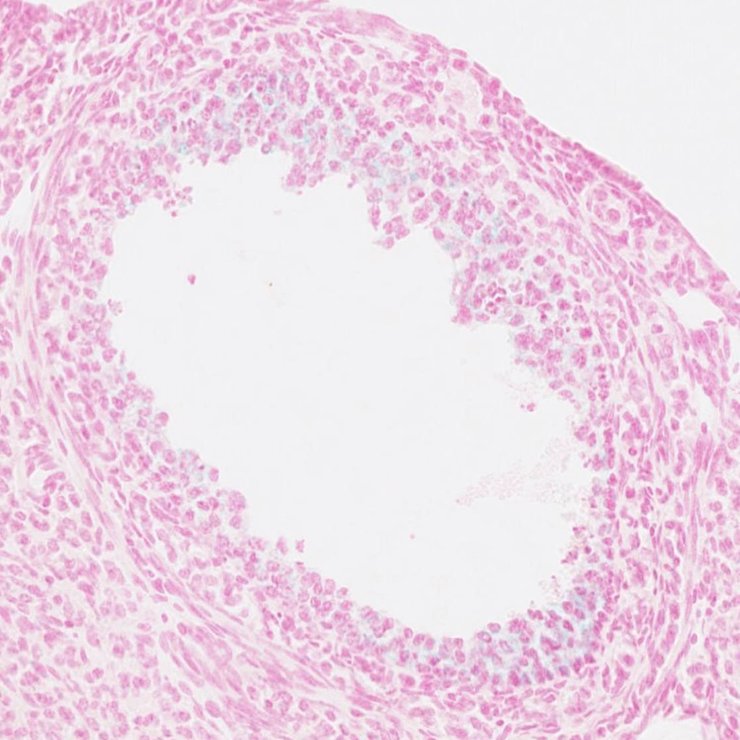

TS28: thymus Present JAX_1798708

Specimen JAX_1798708: postnatal adult; Mmp8tm1.1(KOMP)Vlcg/Mmp8+ (more )

Structure Level Pattern Image Note